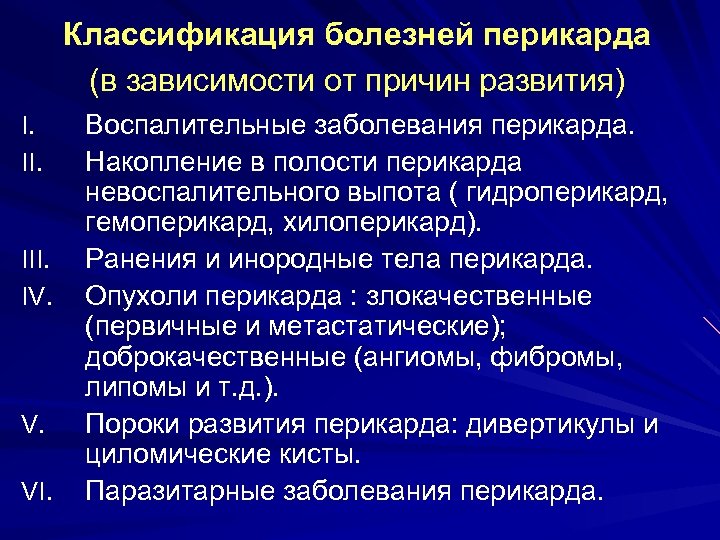

Классификация болезней перикарда (в зависимости от причин развития) I. II. III. IV. V. VI. Воспалительные заболевания перикарда. Накопление в полости перикарда невоспалительного выпота ( гидроперикард, гемоперикард, хилоперикард). Ранения и инородные тела перикарда. Опухоли перикарда : злокачественные (первичные и метастатические); доброкачественные (ангиомы, фибромы, липомы и т. д. ). Пороки развития перикарда: дивертикулы и циломические кисты. Паразитарные заболевания перикарда.